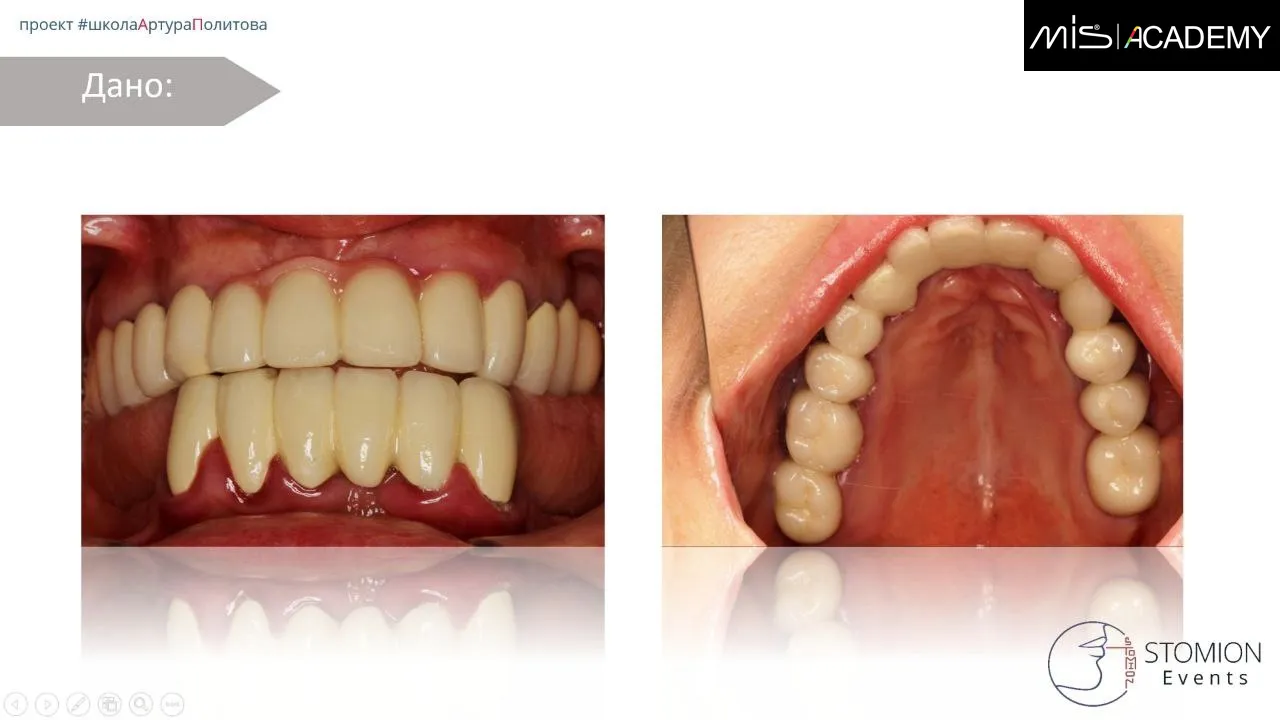

В продолжение предыдущего случая, верхняя челюсть. Удаление не состоятельных и за компанию парочку состоятельных зубов.

— Оставили 4 зуба для опоры НХШ.